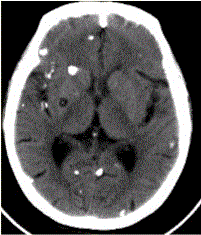

患者男,45岁。头痛、癫痫10余年。查体:无发热,双侧肢体肌力正常。脑电图示双侧额颞叶棘波放电。CT表现如下图。头颅CT检查中,可见囊虫头节钙化,...